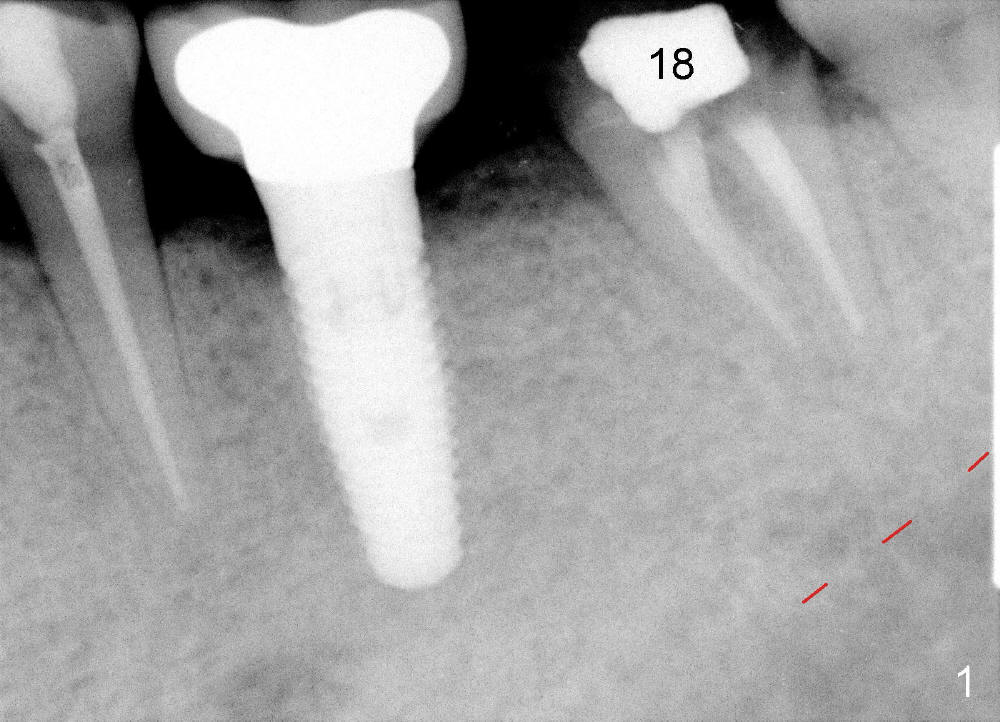

A 63-year-old man has lost a crown from the tooth #18 (Fig.1), which is tender to percussion. The margin is subgingival.

CBCT reveals periapical radiolucency (Fig.2 ^). The tooth appears to be nonsalvageable. The root is 11 mm long. There is 5 mm bone between the fused apex and the inferior alveolar nerve. The prospective implant is going to engage 3 mm out of the 5 mm native bone for primary stability.